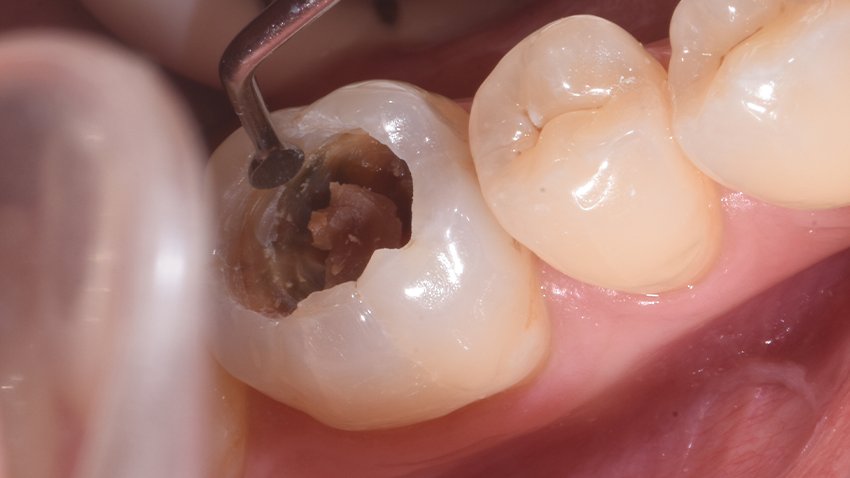

Figure 4: Selective carious tissue removal with a hand excavator (Photo courtesy of Dr. Michal Dekel-Steinkeller)

In cases where we may have removed a little too much carious tissue and are near the pulp – where the bottom of the prep appears pinkish, almost like you can see the pulp through very thin dentin – it’s advisable to place a more biocompatible material as a liner. Vitrebond Plus is an example of an RMGIC that provides the biocompatibility we need, along with good adaptation and adhesion (fig 5 and 6)

Figure 6: 3M™ Vitrebond™ Plus is placed directly on caries-affected dentin (Photo courtesy of Dr. Michal Dekel-Steinkeller)